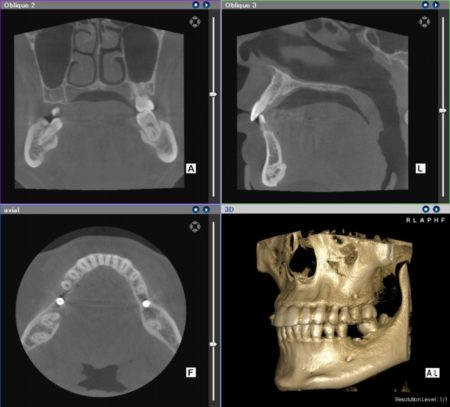

3D画像診断

CT(Computed Tomography)を使って、3D画像のレントゲン写真による診断が可能です。従来のレントゲン写真では見る事の出来ない情報をたくさん得ることができますし、患者様にもわかりやすい画像診断法です。